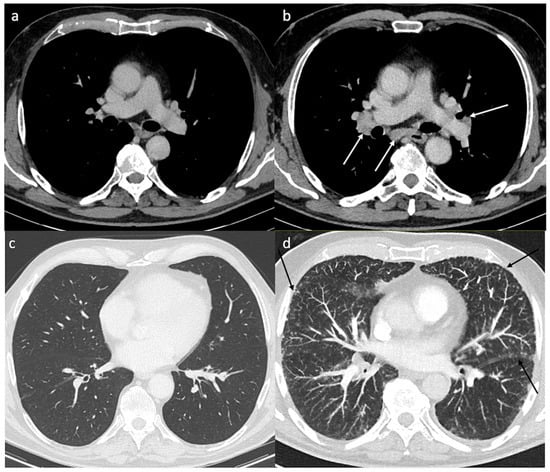

| Radiological features | |

| Consistent radiological signs | 17 (94%) |

| Median time since ICI initiation (min–max) (months) | 2 (1–10) |

| 18-FDG PET/CT; n = 14 | |

| Mediastino-hilar nodes | 14 (100%) |

| Interstitial involvement | 6 (43%) |

| Subcutaneous nodules | 4 (29%) |

| CT scanner; n = 15 | |

| Mediastino-hilar nodes | 11 (73%) |

| Interstitial involvement | 1 (7%) |

| Subcutaneous nodules | 1 (7%) |